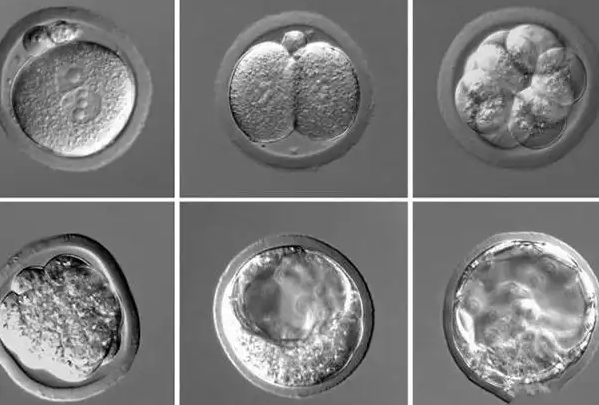

在试管婴儿囊胚培养中,多数囊胚会在第5-6天发育成熟,7天囊胚因发育时间稍晚,常让备孕家庭困惑是否可以移植。实则7天囊胚并非异常胚胎,只要质量达标、母体条件适配,完全具备移植价值,其核心差异仅在于发育节奏,而非潜能优劣。了解7天囊胚的核心特性、移植可行性依据、质量评估标准、适配场景及注意要点,能帮助家庭理性看待,避免因发育时间延迟盲目放弃,科学配合诊疗决策。

7天囊胚指体外培养至第7天形成的囊胚,较常规5-6天囊胚发育节奏稍缓,本质是胚胎个体发育差异导致,并非发育异常。这类囊胚仍能完成细胞分化,形成内细胞团(发育为胎儿)和滋养层细胞(发育为胎盘),具备着床与后续发育的基础潜能。其发育延迟可能与胚胎自身代谢节奏、实验室培养环境、母体卵子质量等因素相关,不直接影响胚胎核心遗传物质与健康度。

7天囊胚的移植可行性,核心取决于质量达标与母体条件适配。从临床数据来看,优质7天囊胚的着床率虽略低于5-6天优质囊胚,但仍显著高于劣质早期胚胎,能为备孕家庭提供有效妊娠机会。人体子宫环境对发育稍缓的囊胚具备良好包容性,只要囊胚形态规整、细胞活性充足,移植后可正常适应子宫内环境,启动着床与发育流程,无需过度担忧“发育慢”影响妊娠结局。

7天囊胚能否移植,关键前提是质量达标,评估标准与常规囊胚一致。依据Gardner分级系统,重点观察囊胚扩张程度(数字4-6级,扩张越充分越好)、内细胞团形态(A-C级,细胞数目多、排列紧密为优)、滋养层细胞形态(A-C级,细胞结构规整为优)。仅优质(如4AA、4AB、4BA)和中等质量(如4CB、4BC)的7天囊胚建议移植,劣质7天囊胚因潜能不足,不推荐移植以避免浪费诊疗机会。